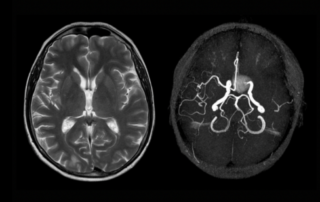

Magnetic Resonance Imaging (MRI); Magnetic Resonance Angiography (MRA):

Additional noninvasive tools, MRI and MRA imaging also require lying face up and motionless in a tube-shaped machine that uses magnetic fields and a special dye injected through an IV in the arm to look closely at the blood vessels of the brain.